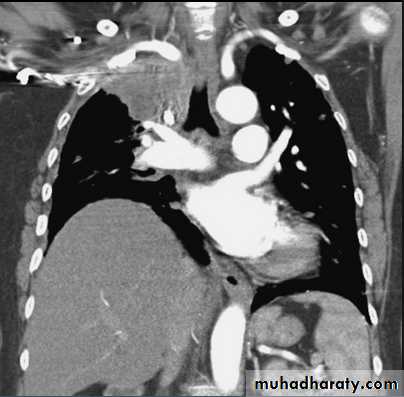

Hodgkin Lymphoma. A. Posteroanterior chest radiograph in a 35-year-old man shows a large, lobulated mediastinal mass. B. Contrast-enhanced CT at the level of the aortic arch shows bulky anterior and middle mediastinal lymphadenopathy